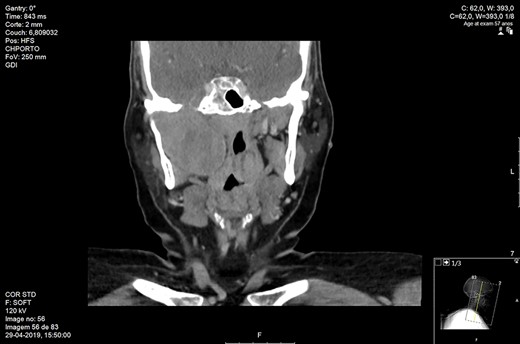

The patient underwent a CT neck revealing a bulky oval right parapharyngeal lesion, well-defined, with 41 × 51 × 54 mm (Fig. 1). The mass remodeled the pterygoid processes and mandibular ramus, extending up to the skull base, increasing oval foramen without intracranial invasion. It deformed the oropharyngeal and nasopharyngeal cavities without airway compromise.

Maxillofacial coronal CT. Right parapharyngeal mass with 54 mm of craniocaudal dimension and 51 mm of transversal dimension.